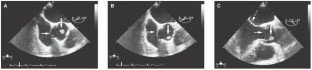

Background A 75-year-old male with a history of myocardial infarction and recent transient ischemic attack was referred to a cardiology clinic for preoperative evaluation before a cystectomy. Transthoracic and transesophageal echocardiography revealed a mobile mass on the right coronary cusp of the aortic valve. Multislice CT demonstrated a significant narrowing in the proximal left anterior descending coronary artery.

Investigations Physical examination, chest radiography, laboratory testing, electrocardiography, transthoracic and transesophageal echocardiography, multislice-CT coronary angiography, pathological and histological examination of the surgically excised tissue.